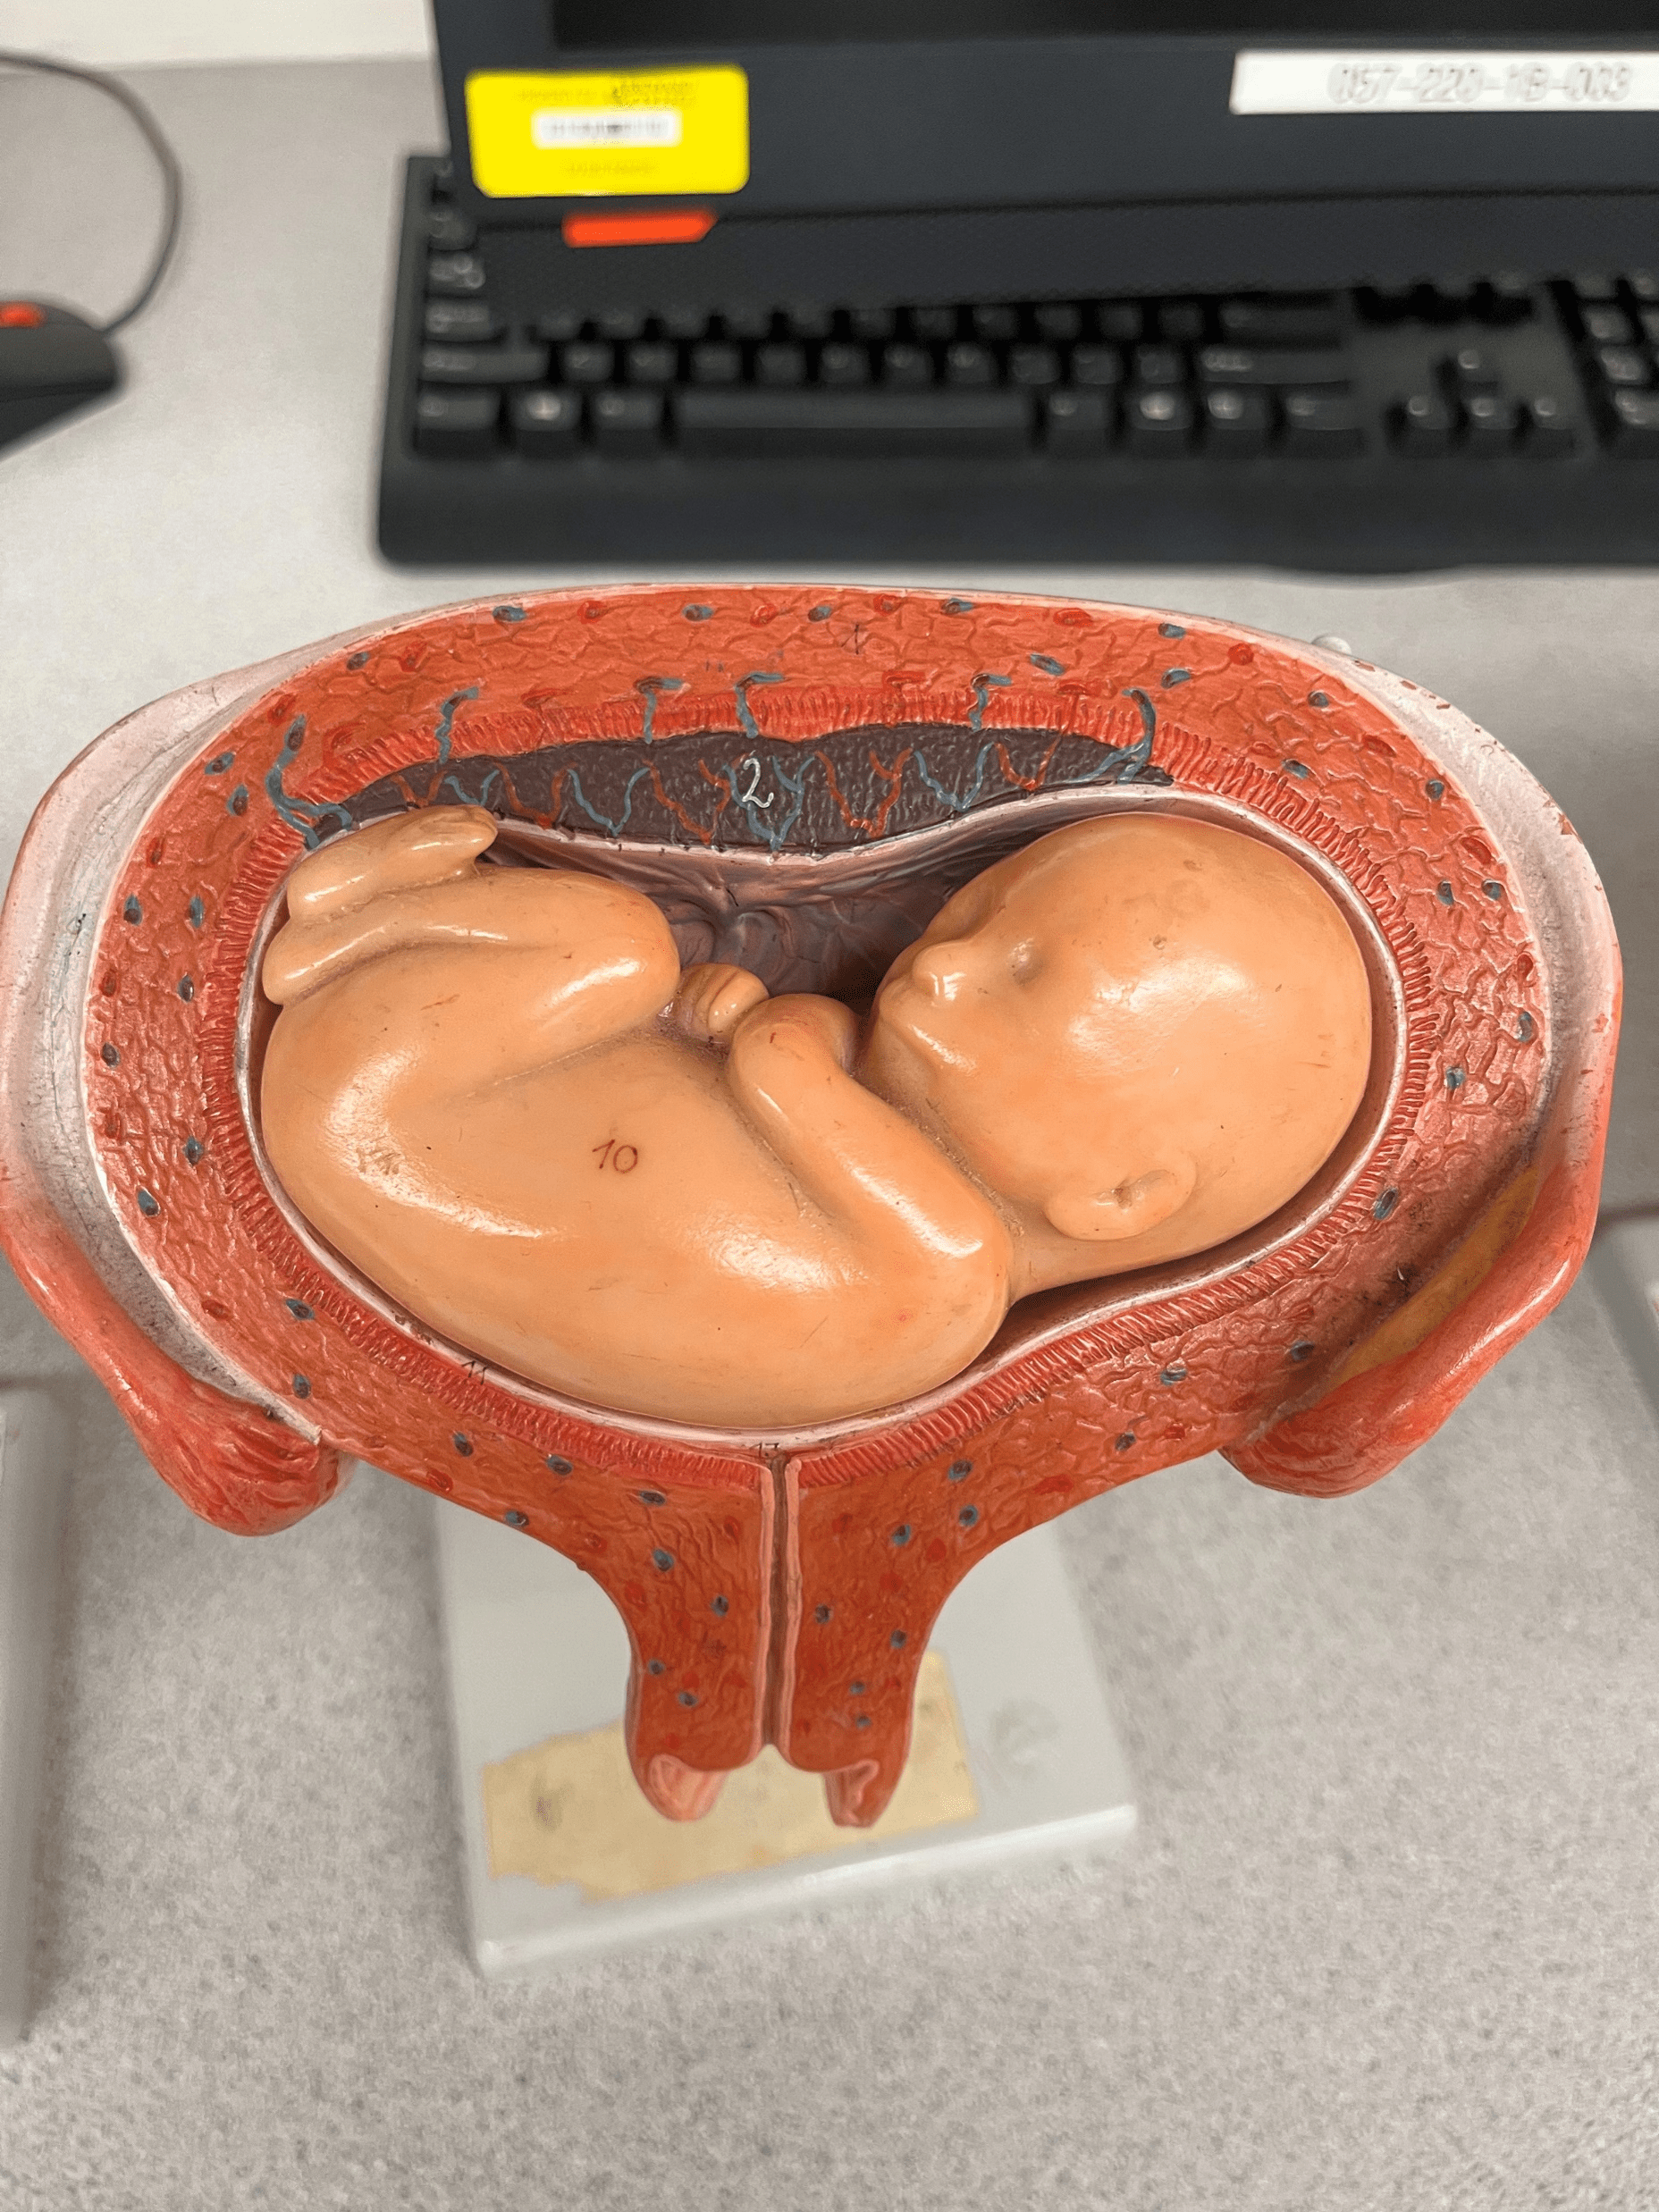

prone position

• Model of the developing fetus in the uterus.

• The position in which the fetus faces downwards.

• The position in which the fetus faces downwards.

16

New cards

breech position

• Model of the developing fetus in the uterus.

• The position in which the feet face downwards.

• The position in which the feet face downwards.

17

New cards

dorsal position

• Model of the developing fetus in the uterus.

• The position in which the fetus faces upwards.

• Also known as the supine position.

• The position in which the fetus faces upwards.

• Also known as the supine position.

18

New cards

normal position

• Model of the developing fetus in the uterus.

• The position in which the head faces downwards.

• Also known as the vertex position.

• The position in which the head faces downwards.

• Also known as the vertex position.

19